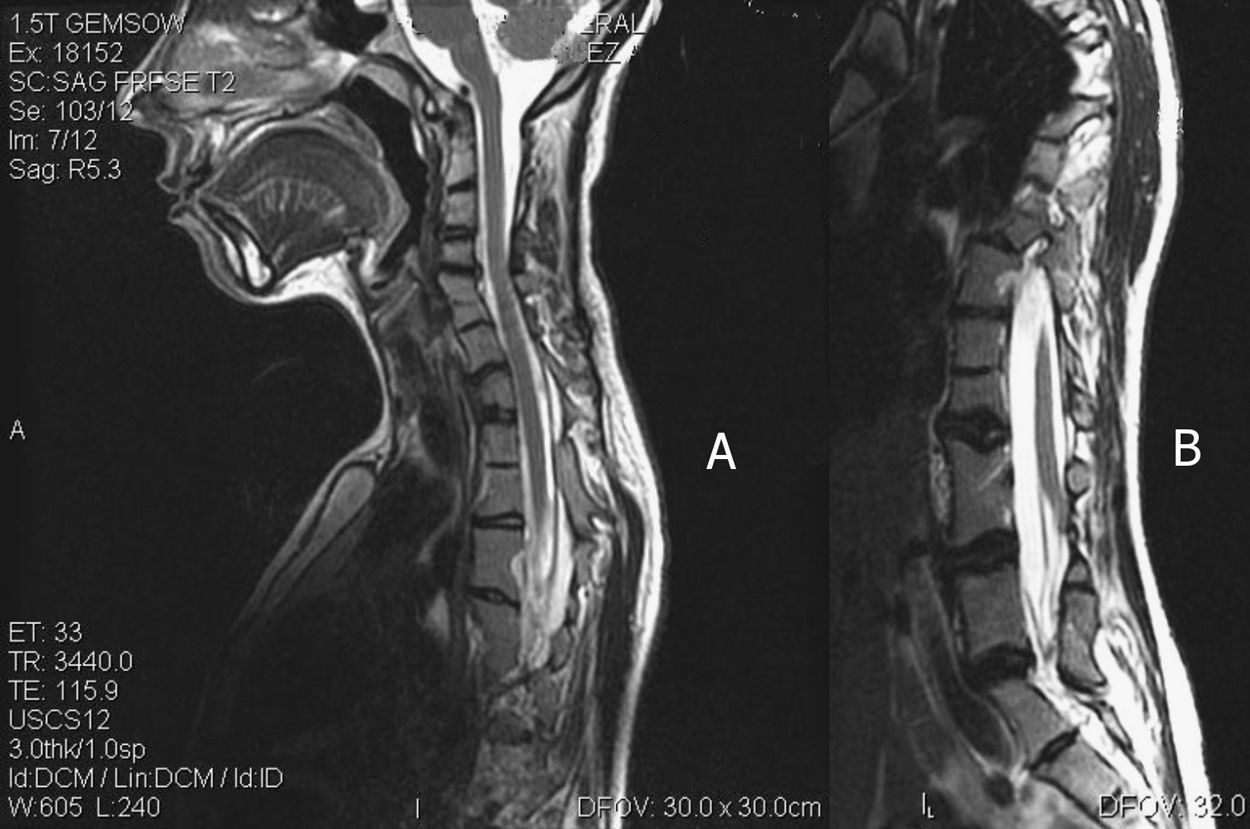

Las displasias vertebrales son defectos del desarrollo que afectan principalmente a los cuerpos vertebrales, dando lugar a graves deformidades de la columna vertebral y de la caja torácica, en forma de escoliosis y cifoescoliosis congénitas. Pueden ser clasificadas en fallos de la formación, fallos de la segmentación o combinación de ambos. La localización y el tipo de defecto vertebral determinarán la gravedad de la curva patológica.

Dichas anomalías pueden aparecer aisladas o asociadas a defectos neurales, viscerales y/o en las extremidades que deben ser descartados en el momento del diagnóstico, solicitando estudios genéticos y de imagen adicionales. El diagnostico precoz, así como el tratamiento rehabilitador con un exhaustivo seguimiento, son de vital importancia para prevenir la progresión de la escoliosis y las posibles complicaciones pulmonares.

Presentamos un caso clínico muy poco frecuente, de múltiples anomalías vertebrales asociado a Síndrome de Rokitansky en una mujer que desarrolló escoliosis durante la pubertad.